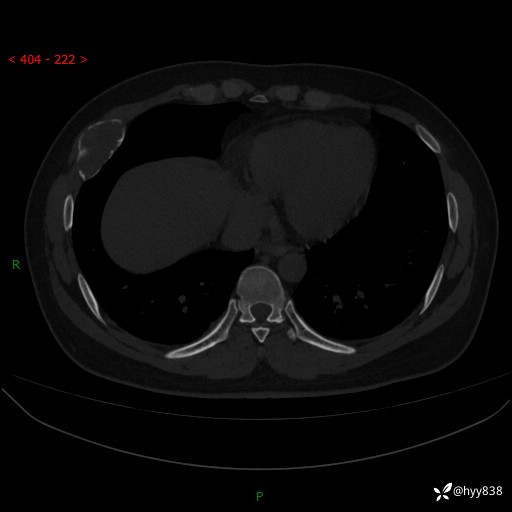

年轻小伙,右侧胸部疼痛4天余。病理科说肯定不是骨纤,那是啥---结果公布~

性别:男

年龄:24岁

主诉:右侧胸部疼痛4天余。

现病史:患者约4天前突发右侧胸部疼痛,无瘙痒,无头痛、头晕,无心慌、胸闷、呼吸困难、咳嗽、咳痰、咯血,无腹痛、腹胀等不适,未作进一步诊治。于2024年5月外院行胸部CT平扫示右侧肋骨骨质改变。现为求进一步治疗,遂于我院就诊。门诊以“胸壁肿物”收入我科。 患者自起病以来,精神可,睡眠可,饮食可,大小便正常,体重无明显改变。

胸部CT平扫